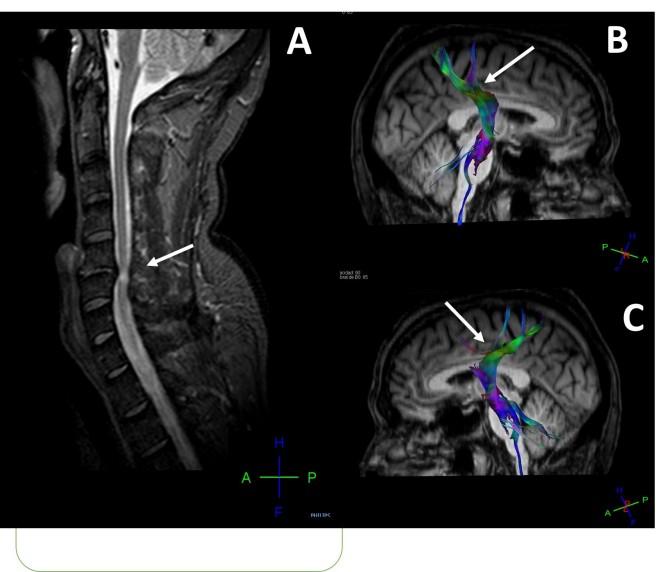

Los investigadores han aplicado herramientas y técnicas de neuroimagen médica avanzadas para tratar de entender mejor lo que sucede en el cerebro de pacientes crónicos con lesiones compresivas por hernias cervicales. Estas técnicas han permitido estudiar tanto la corteza cerebral como las fibras nerviosas de sustancia blanca y los patrones de conexión entre las distintas áreas cerebrales, lo que permite detectar cambios patológicos no observables en los estudios de resonancia magnética convencionales.

“Hemos demostrado que existen cambios a nivel cerebral y en las vías de comunicación de las señales cerebrales que se manifiestan sobre todo por atrofia cortical y daños en la corteza sensorial y motora” explica Eduardo Fernández Jover, coautor de la publicación y director del Grupo de Neuroingeniería Biomédica de la UMH y del CIBER-BBN. “Estos cambios se desconocían hasta ahora y pueden ayudar a comprender mejor la evolución clínica de muchos pacientes y abrir nuevas vías de diagnóstico y tratamiento de esta patología tan frecuente” añade.

Daño cerebral en pacientes con hernias cervicales. (Imagen: CIBER)